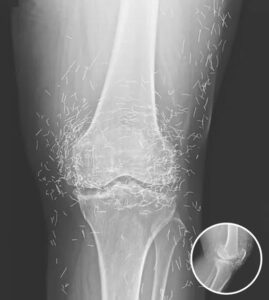

Doctors Stunned After Looking At This X-Ray Of Woman Suffering Joint Pain

A routine X-ray revealed an unexpected surprise when doctors examined the knees of a 65-year-old woman suffering from severe joint pain. What they found was nothing short of astonishing — hundreds of tiny gold needles embedded deep in her tissue. The woman, from South Korea, had been battling osteoarthritis for years. The painful condition breaks […]